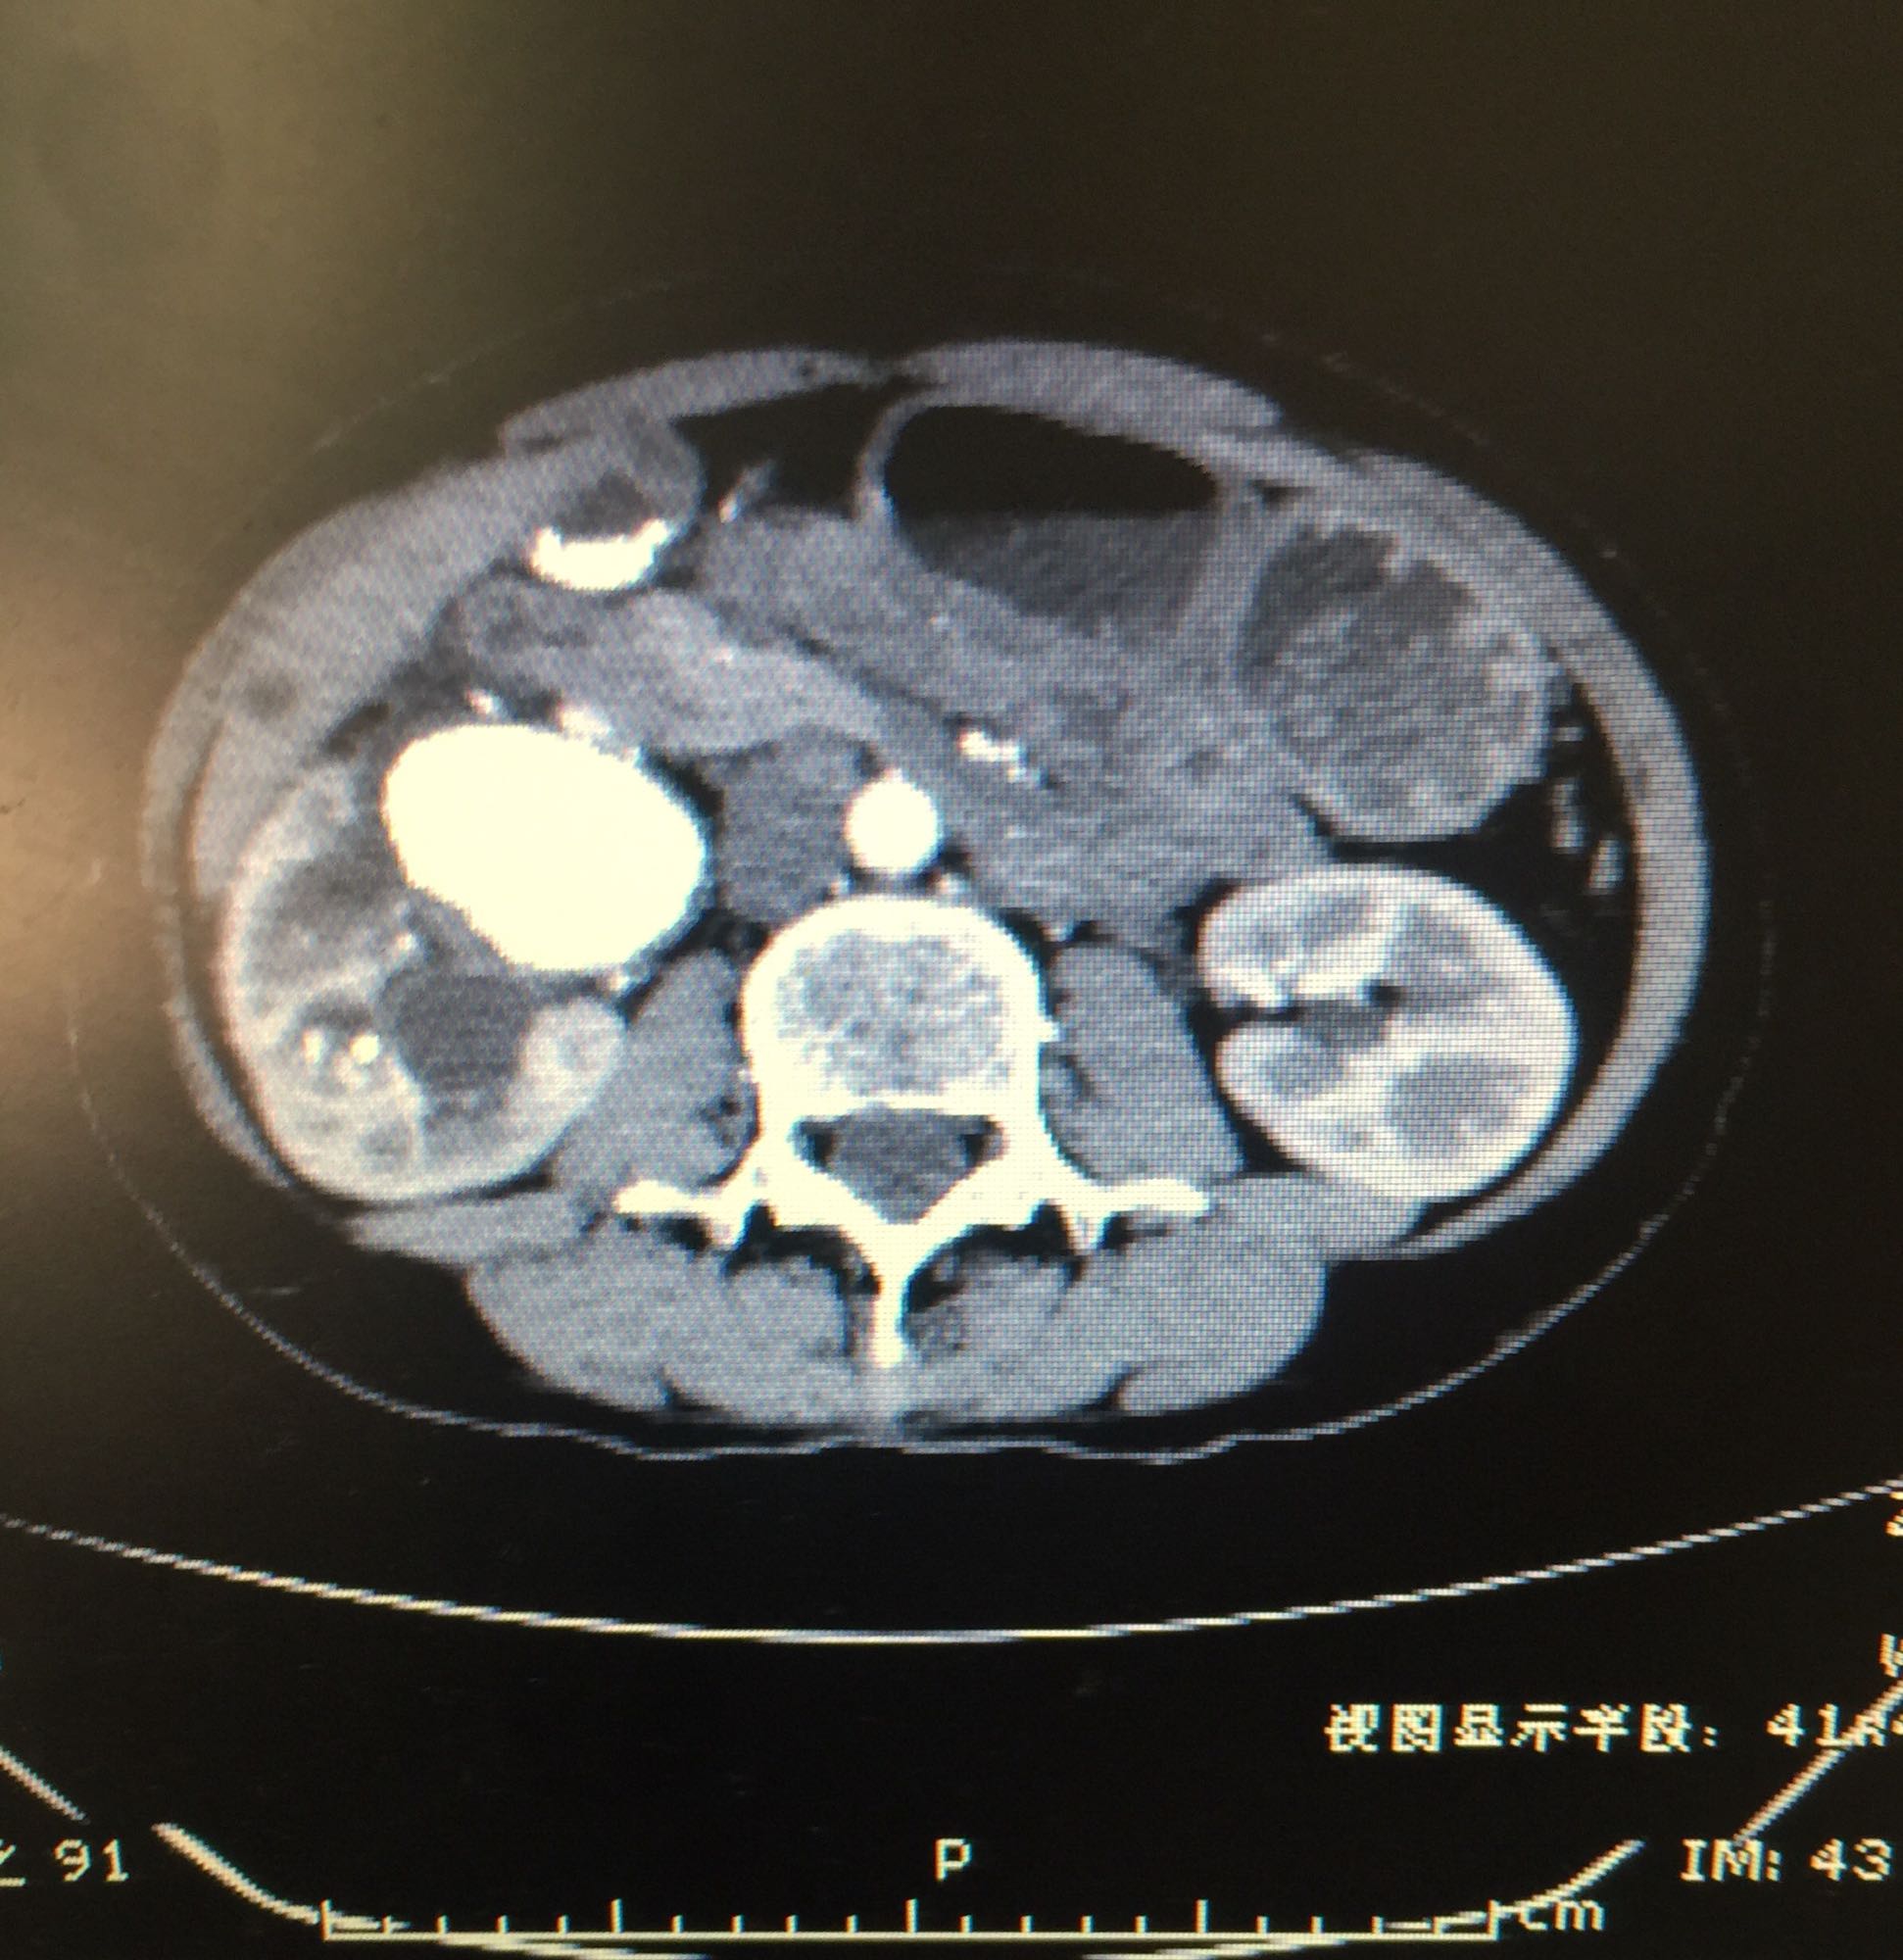

右侧肾脏巨大铸型结石一例

肾盂积水伴输尿管肾盂连接处梗阻 肾结石

60余岁老年男性 因右侧腰痛伴发热1周入院 1周前开始出现右侧腰部胀痛,伴低热,无尿频尿急及肉眼血尿,无其他不适症状 既往高血压,无糖尿病及其他病史

查体右侧肾区轻度叩痛,余症状阴性 辅助检查尿白细胞+++,肾功正常,甲状旁腺激素正常,钙磷比例正常范围

右侧肾脏巨大铸型结石,右肾盂输尿管连接部狭窄? 拟完善GFR测定后决定下一步治疗方案,目前倾向于开放手术。

该患者结石大,且负荷大部分位于肾盂,肾盂几乎被填满,所以考虑是否有右侧输尿管肾盂连接部狭窄可能,结石负荷大,结合上述情况可行开放手术,一期整形 。 但若为UPJO,患者肾脏积水轻,肾脏皮质厚,肾功影响小,可能性相对小。行PCN结合超声吸附,一期清理肾盂内结石应该问题不大。 对于该患者的治疗,不知大家意见如何?